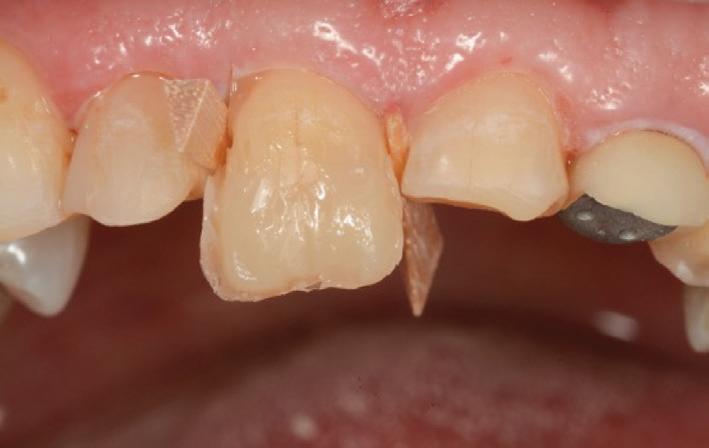

The teeth were cleaned of plaque and the chipped and unsupported enamel was removed (Figs. 4, 5). Fine bevels were placed to facilitate composite adhesion.

Small, 1/2 round bur undercuts were placed, and all of the exposed

dentine (and the old crown) were micro-etched with the Rondoflex 360 sandblaster, using 27um particles (Figs. 6, 7).